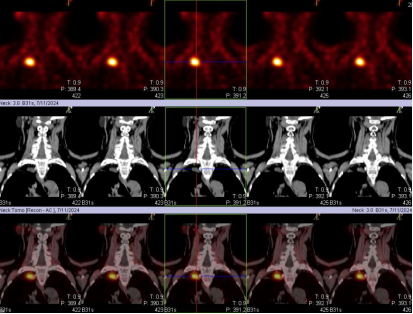

甲状旁腺显像正常图像: